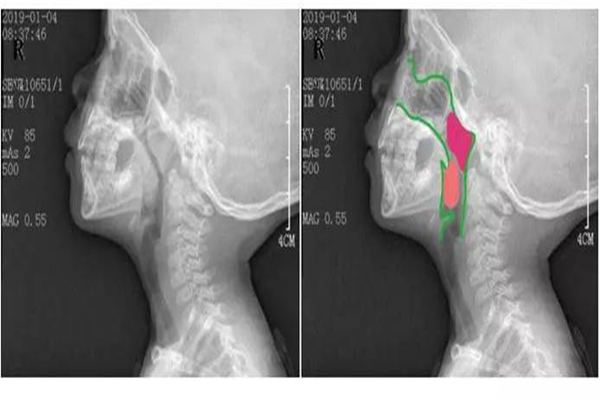

7月21日,桐桐的父母帶著他來到西電集團醫(yī)院進行全面檢查。經(jīng)檢查,桐桐為扁桃體腺樣體肥大;慢性鼻炎;堵塞鼻咽部4/5。